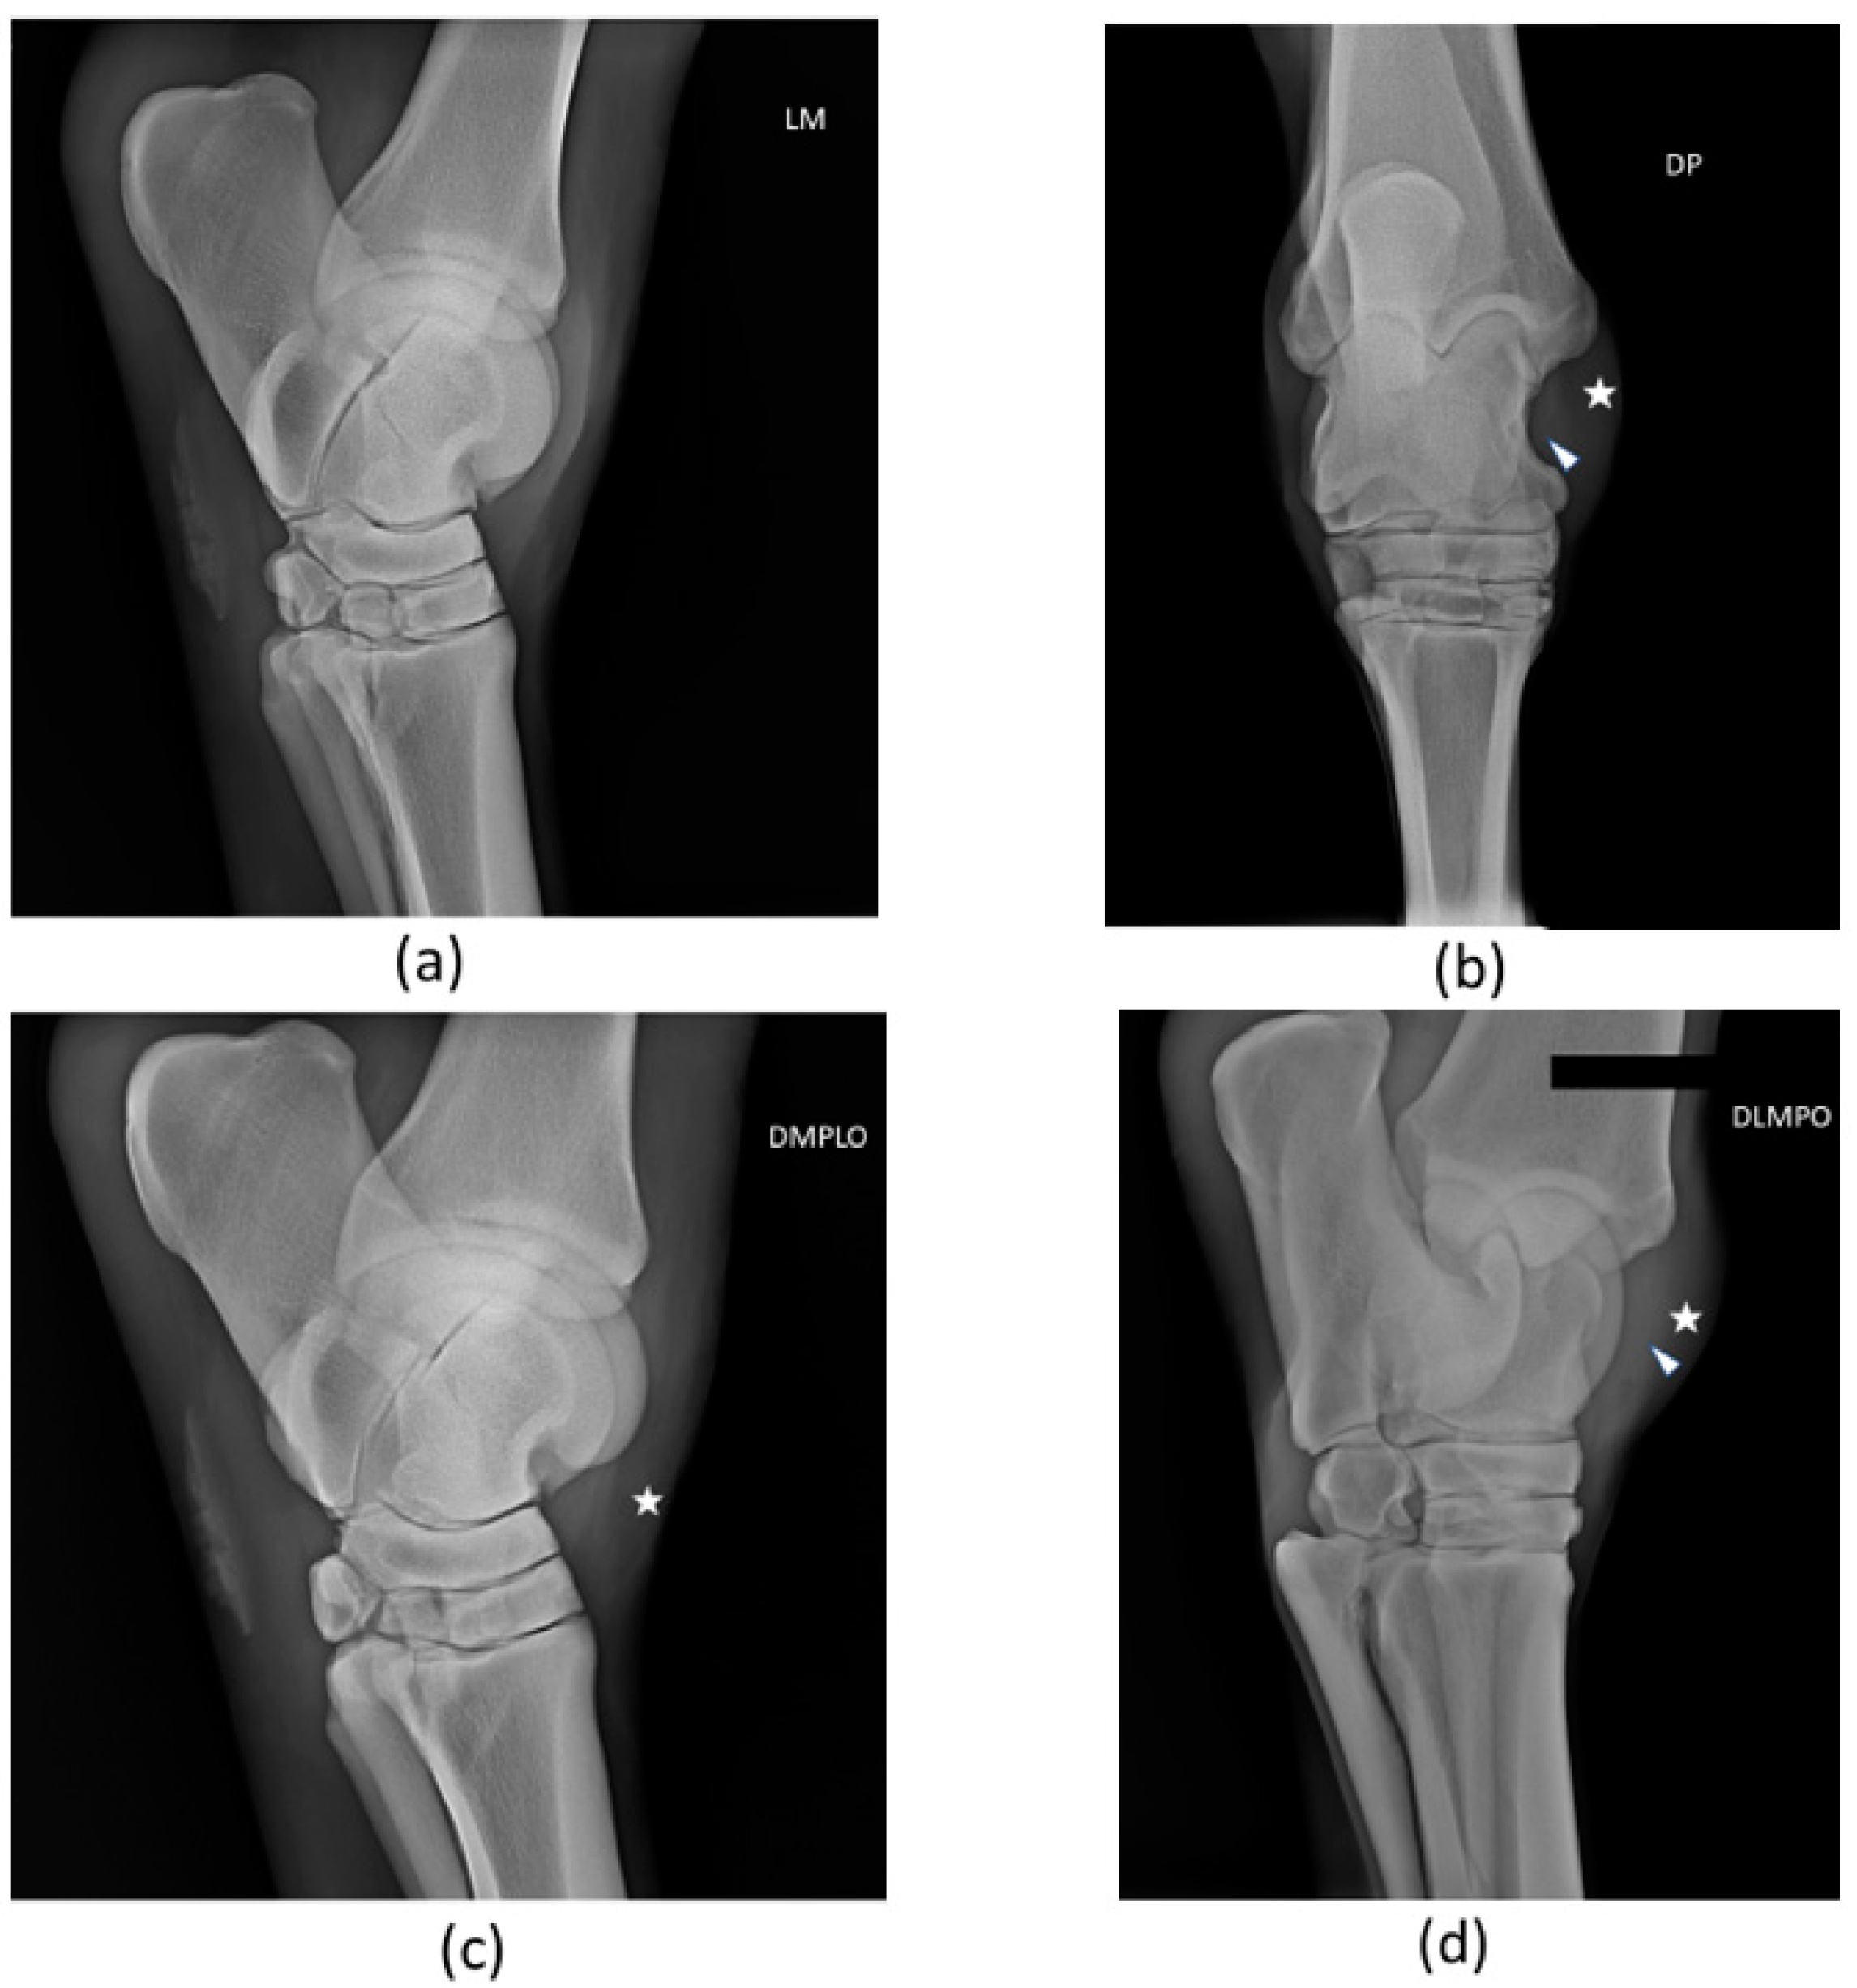

A radiological examination was performed. The horse did not present significant articular abnormalities within the tarsocrural joint. There was tarsocrural joint distension, soft tissue distension, and slight evidence of tissue thickening at the injured long medial collateral ligament. Radiographs are presented in Figure 3. X-ray examination was not carried out again during the follow-up period.

Figure 3.

Radiographic views of patient’s right tarsus: (a) Lateromedial (LM), (b) Dorsoplantar (DP), (c) Oblique dorsomedial-plantarolateral (DMPLO), (d) Oblique dorsolateral-plantaromedial (DLPMO). The white head of the arrow (△) points to increased radiopacity of the long medial collateral ligament, and the star (*) signals soft tissue swelling and joint distension. There are no significant radiological alterations of articular surfaces.